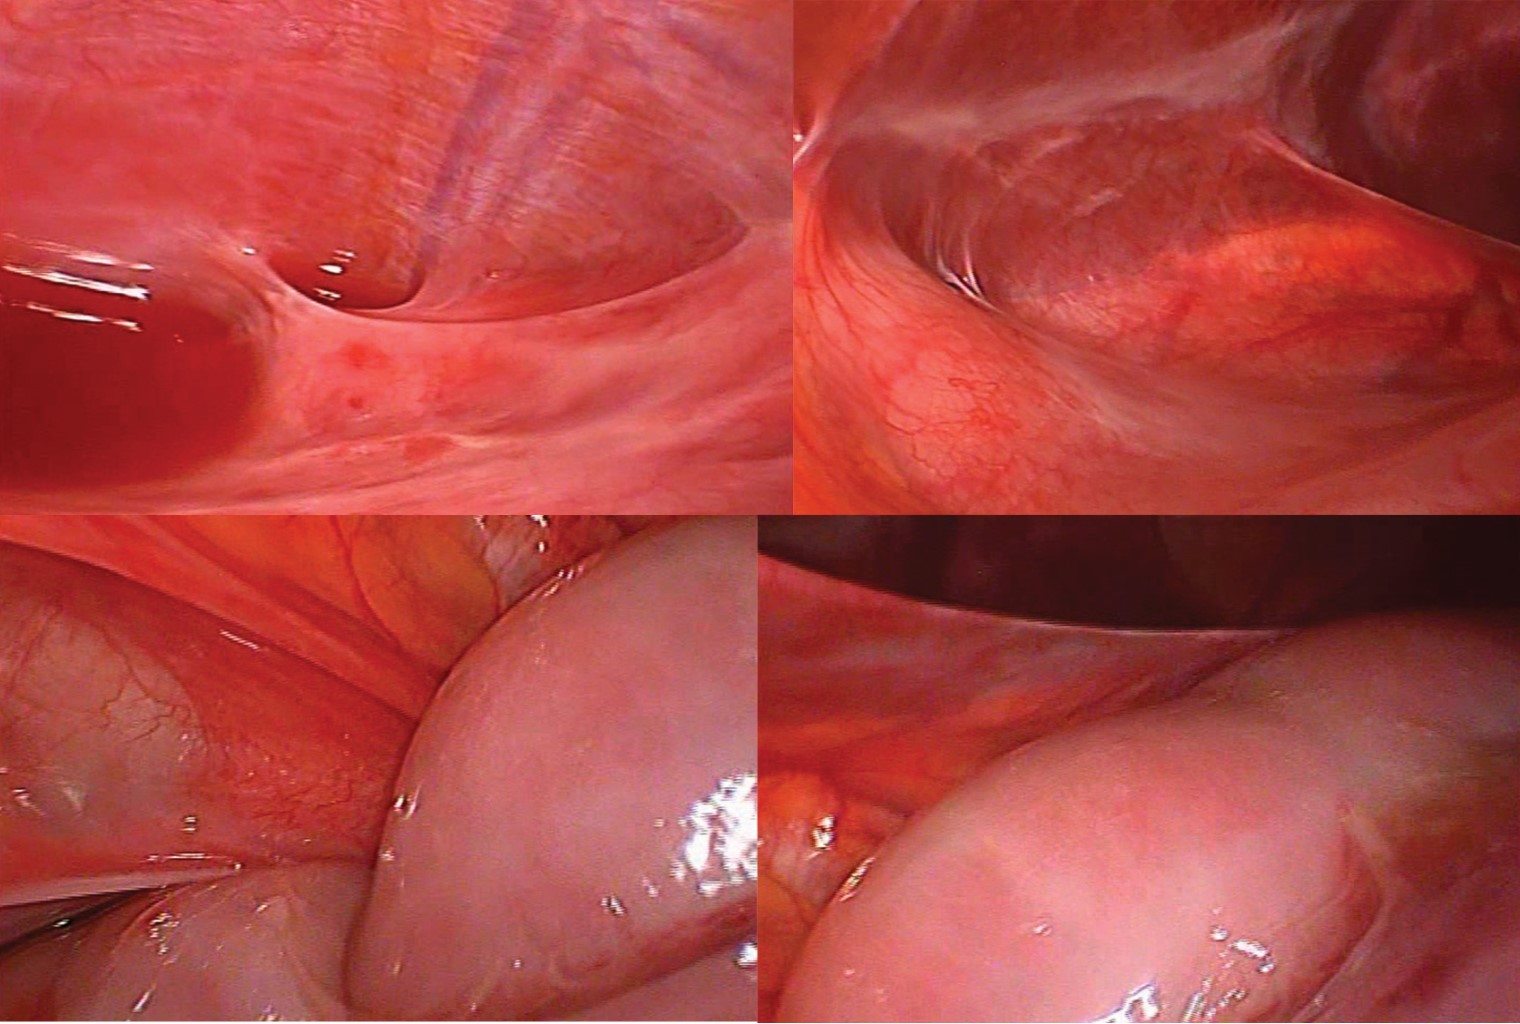

A diagnostic laparoscopy was decided due to a lack of resolution and diagnostic certainty of an intestinal occlusion syndrome. A laparoscopic approach was used with a 10 mm umbilical port with Hasson or open technique. Peritoneal mesenchymal fibrotic mesenchymal tissue was found fixing the intestinal loops from the Treitz angle to the ileocecal valve thus limiting its movement. Distension was present forming a second pseudo peritoneal pouch, with serohematic fluid (40 ml). The surface of the pseudo-pouch was not granulomatous and separated from the greater peritoneal cavity (Figure 2). It was decided to convert to open surgery, through a supra infra umbilical midline incision. A sample of cavity fluid was taken, then the release of fibrotic tissue which surrounded 75% of the small bowel from the jejunum to the terminal ileum. A separation plane was identified between the mesenchymal tissue and the intestinal visceral peritoneum (Figure 3). There were no ischemic changes in the bowel loops, which had preserved motility, and no enlarged lymph nodes in the mesentery. A Jackson-Pratt drainage was placed into the pelvic cavity and the abdomen closed.

The patient evolved well. He mentioned symptomatic improvement as compared to the preoperative state. Oral feedings started 24 hours after the procedure. Only serohematic fluid came through the drainage during the first days. On radiological control, standing and decubitus abdominal films showed adequate intestinal gas distribution. The patient was discharged on the third postoperative day and sent to the hospital outpatient clinic for follow-up and control. At one year follow-up, he had gained weight and had no clinical evidence of recurrence of obstructive symptoms. The histopathological report was of a serous mesothelial cyst, with moderate chronic inflammatory changes in the omentum and peritoneal fluid (Figure 4).